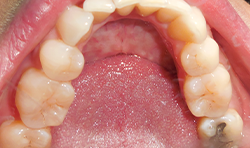

A patient presented to the practice complaining that her husband and daughter have told her she snores, at times wakes up gasping for air, short of breath and appears to be choking. The patient also stated she hasn’t slept well for the last 20 years.

Our clinical findings included a body mass index of 27, a constricted maxillary arch, retrognathic mandible, high palatal vault, tooth occlusal wear, Class IV Mallampati restricted airway and a familial history of sleep apnea (Figs. 1–3).

When the patient was younger, she had four premolar extractions during orthodontic intervention. These had now slightly relapsed, causing anterior crowding and reclining of her premolar and molars. In addition to the snoring, the patient was diagnosed with Hashimoto’s disease, which has also been correlated with obstructive sleep apnea.6 She also had a previous diagnosis of periodic limb movements of sleep (PLMS), for which she was on a higher-than-normal dosage of clonazepam. Clonazepam has also been linked to causing sleep apnea.7,8